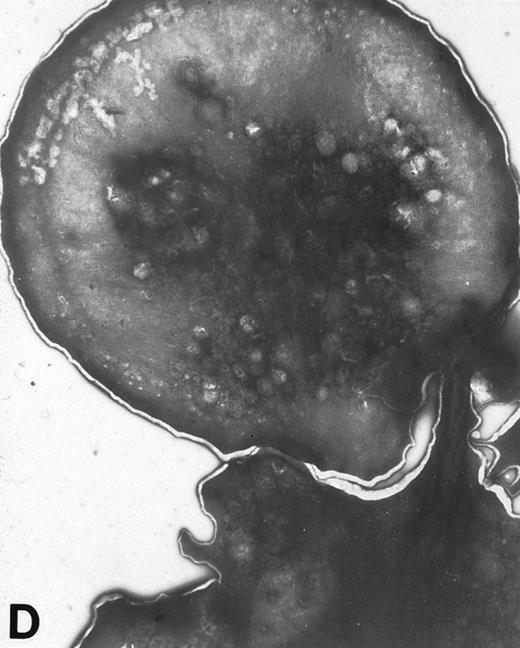

(A) Representative resting WF rat platelets prepared identically to resting Wistar platelets in Fig 2. (B through E) WF rat platelets allowed to adhere to Formvar-coated, carbon-stabilized grids from 30 seconds to 30 minutes, and subsequently fixed and stained with uranyl acetate. (B through E) illustrate the forms characteristic of WF rat platelet spreading, including platelets with stubby filopodia (B), lamellipodia (C), or fully spread forms (D and E). (E) shows the spread margin of a WF platelet at higher power. The arrowheads indicate microtubules and the asterisk shows the dense peripheral weave at the platelet margin. (B) 30-second adherent sample, (C) 1-minute adherent sample, (D and E) 30-minute adherent sample. (A through D, original magnification ×7,000; E, original magnification ×19,000).